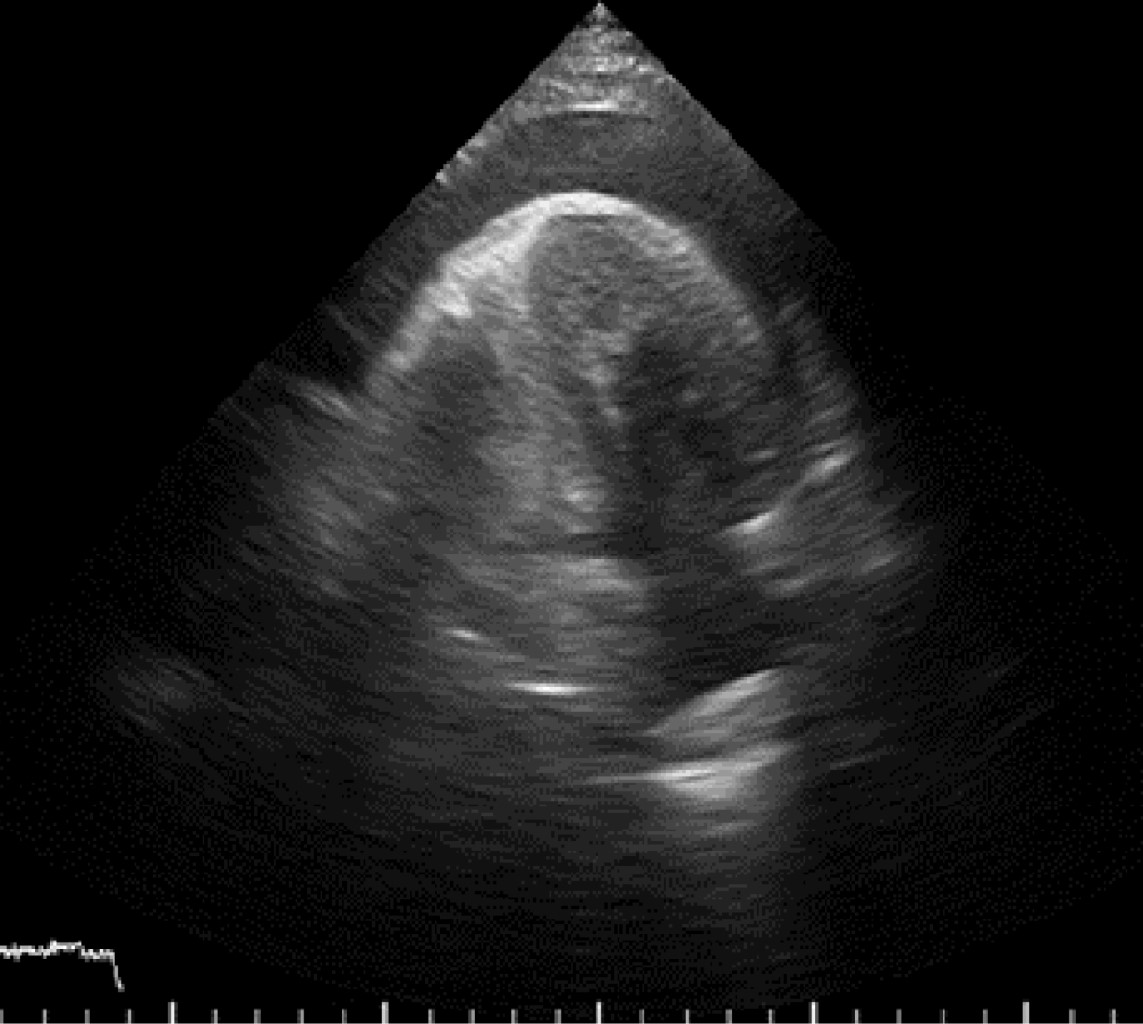

Ruptura cardiaca durante ecocardiograma de estrés con dobutamina como estratificación posterior a infarto agudo al miocardio

El ecocardiograma de estrés con dobutamina es ampliamente utilizado en la estratificación posterior a un infarto agudo al miocardio. Se han reportado complicaciones que pueden ser potencialmente mortales, siendo las arritmias ventriculares las más frecuentes. La ruptura cardiaca es una complicación rara, pero fatal. Se presenta el caso de un masculino de 68 años con un infarto inferior sin estrategia de reperfusión, el cual fue sometido a un ecocardiograma de estrés con dobutamina a los seis días del infarto. Durante la recuperación inicial el paciente presenta ruptura cardiaca por presencia de derrame pericárdico de aspecto hemático y disociación electro mecánica. Se realizó pericardiocentesis de urgencia, finalmente falleciendo el paciente. En la literatura se ha reportado el infarto inferior reciente y una zona discinética como las características de alto riesgo para presentarse. La selección adecuada del paciente, un ecocardiograma basal sin características de riesgo para ruptura y el tiempo de realización del estudio posterior al infarto puede disminuir la incidencia de esta complicación.

Figura 3